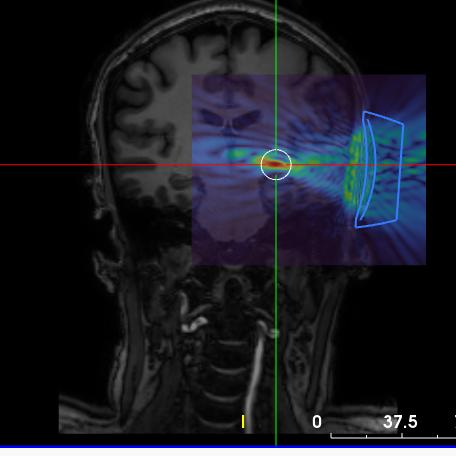

Low Intensity Focused Ultrasound for Parkinson’s Disease Tremor

In this study, we aim to compare the effects of targeting two different brain regions, the traditionally treated VIM and the zona incerta (ZI), using LIFUS for tremor control in Parkinson’s disease. Past research has shown that the ZI may be an important area for treating tremor and other Parkinson’s symptoms like stiffness and uncontrolled movements. Our goal is to understand how these brain regions contribute to Parkinson’s tremor and how the network responds to LIFUS. The knowledge gained will contribute to developing more effective treatments for Parkinson’s disease in the future.

Principal Investigator: Dr. Martin McKeown

Primary contact: Maggie Vuong

604-822-0345

maggie.vuong@ubc.ca